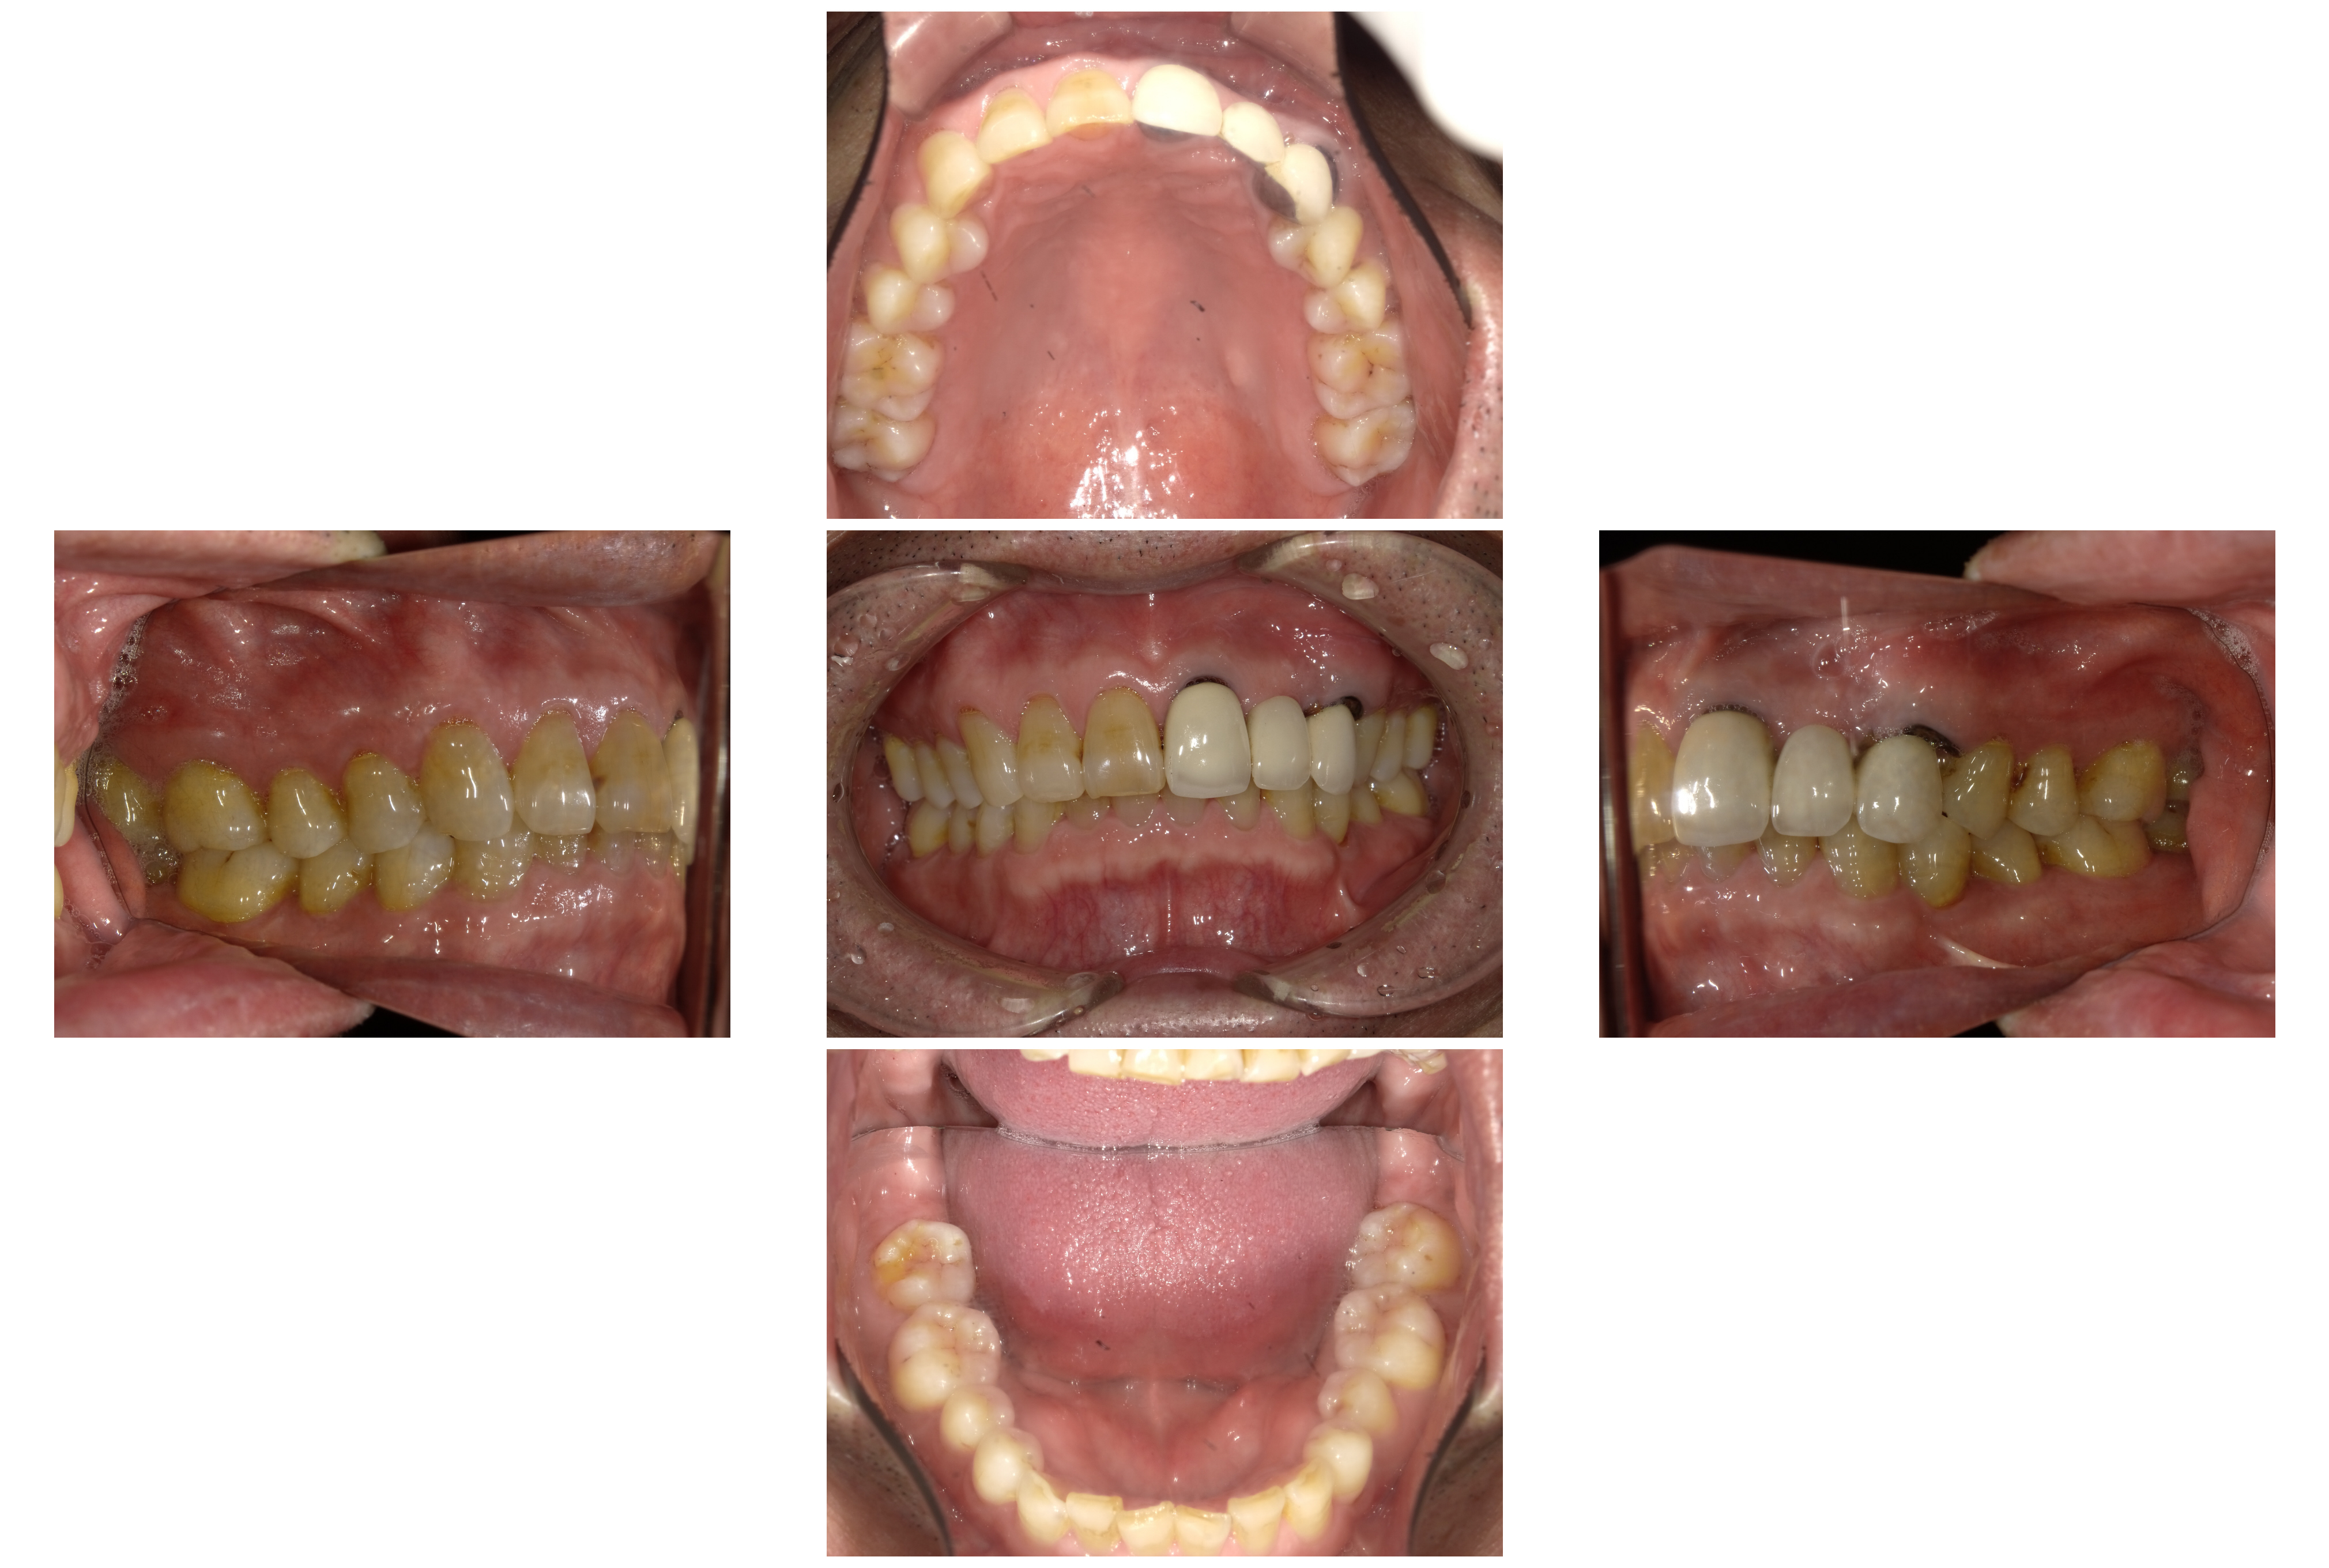

術後

インプラント治療期間:約4か月

費用:¥1,177,000-(税込)

インプラント体 2本

インプラント上部構造物(セラミックブリッジ)

インプラントの仮歯